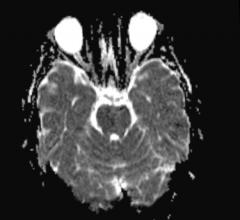

Today, perfusion MRI is primarily applied when diagnosing strokes and tumors. It measures which brain areas receive insufficient blood supply after a stroke occurs. It can also assess the viability and functionality of the liver and kidneys. Furthermore, the method can visualize which regions of a tumor are supplied with the most blood. In these areas, the ulcer grows the fastest, but is also more receptive to therapeutic treatment – helpful information for radiation therapists.

A new alternative that does not require contrast agents has recently emerged, called arterial spin labeling. An MR scanner magnetically tags the blood flowing through an organ. The scanner ‘flips’ the original orientation of the atoms in the magnetic field. Then, it follows the magnetically tagged blood on its way through the brain vessels. “The method without contrast agents is non-invasive and less stressful for patients,” said Günther. “For patients who are frequently examined, some contrast agents run the risk of accumulating in the body.”